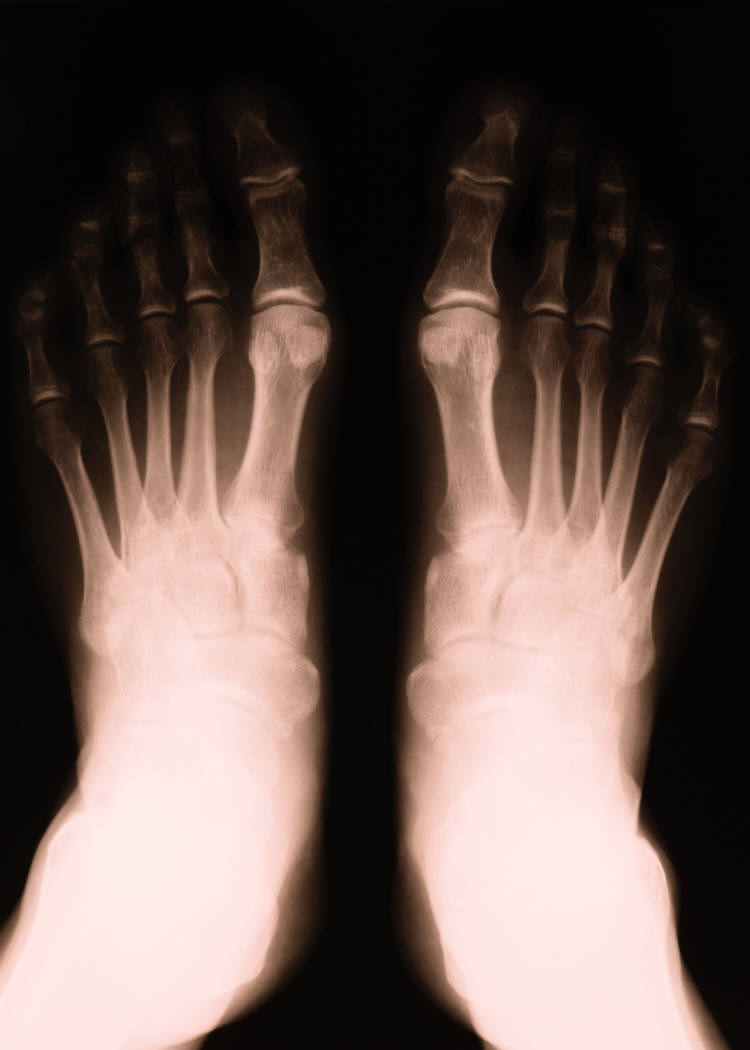

- Bunions

- Bunionettes(Tailor's Bunions)

- Fractures and Stress Fractures

- We are also proud to offer in-house Digital X-ray's.